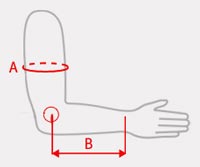

Tabela rozmiarów

| Rozmiar | (A) Obwód ramienia | (B) Długość od nadkłykcia bocznego kości ramiennej do nadgarstka | Sposób dokonywania pomiaru |

|---|---|---|---|

| Uniwersalny | min 28 – max 35 cm | min 22 – max 31 cm |  |

| Całkowita wysokość ortezy | Całkowita długość ortezy |

|---|---|

| min 25 cm – max 28 cm | min 43 cm – max 52 cm |